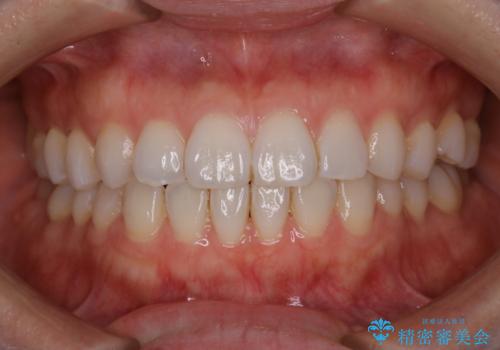

PMTCで清潔感ある口元に

担当医 歯科衛生士